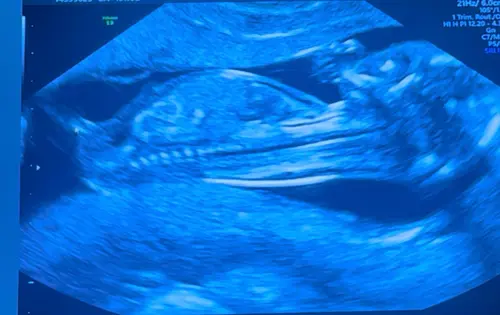

13 weken. Wat denken jullie?

Beentje zit ervoor